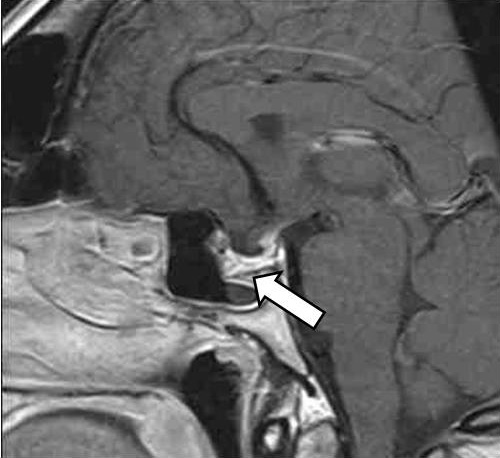

С 11 по 17 января 2023 г. – госпитализация в эндокринологическое отделение БУЗ УР «1 РКБ МЗ УР». При осмотре пациентка предъявляет жалобы на набор веса на 13 кг за последние 2 года, избыточную потливость, храп, боли в суставах пальцев рук, коленных суставах, повышение артериального давления до 145/100 мм рт. ст., сопровождающееся головными болями. На постоянной основе пациентка принимает левотироксин натрия 150 мкг/сут; гидрокортизон 20 мг/сут вместо рекомендованных ранее 15 мг/сут (забыла снизить дозу препарата), эстрадиол + дидрогестерон 1/10 мг (1 таблетка вечером внутрь). По данным УЗИ щитовидной железы от 13.01.2023 (в проекции долей и перешейка ткань щитовидной железы не визуализируется, ложе без особенностей, шейные лимфоузлы не увеличены), лабораторных обследований (ТТГ – 0,13 мкМЕ/мл (0,4–4,0), тиреоглобулин менее 0,20 нг/мл, антитела к тиреоглобулину менее 20,0 МЕ/мл от 12.01.2023) зарегистрирована биохимическая ремиссия папиллярного рака щитовидной железы. На МРТ от 12.01.2023 визуализировано вторичное «пустое» турецкое седло как исход апоплексии гипофиза, данных за рецидив аденомы не получено (рис. 3).

Рис. 3. Магнитно-резонансная томография гипофиза с контрастным усилением. «Пустое» турецкое седло (указано стрелкой)

По данным лабораторного обследования от января 2023 г. ИФР-1 – 171,3 нг/мл (83–220), базальный уровень СТГ – 1,56 нг/мл, что позволило констатировать ремиссию акромегалии. Пациентка осмотрена офтальмологом – заподозрена частичная атрофия зрительного нерва, рекомендована его оптическая когерентная томография. По результатам биохимического анализа крови повторно была выявлена дислипидемия (от 12.01.2023 липопротеиды низкой плотности – 3,62 ммоль/л), назначена терапия статинами. По данным эхокардиографии от 13.01.2023: систолическая функция левого желудочка удовлетворительная, диастолическая дисфункция левого желудочка по I типу, размеры камер сердца в норме, недостаточность митрального клапана I степени, недостаточность трикуспидального клапана I степени.